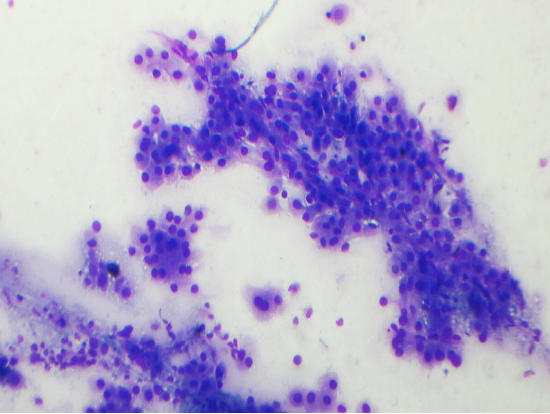

CYTOPATHOLOGY

Figs 1 and 2 from a mass in the right hypochondriac region.

Make your diagnosis.

Fig 1 : Giemsa x 100